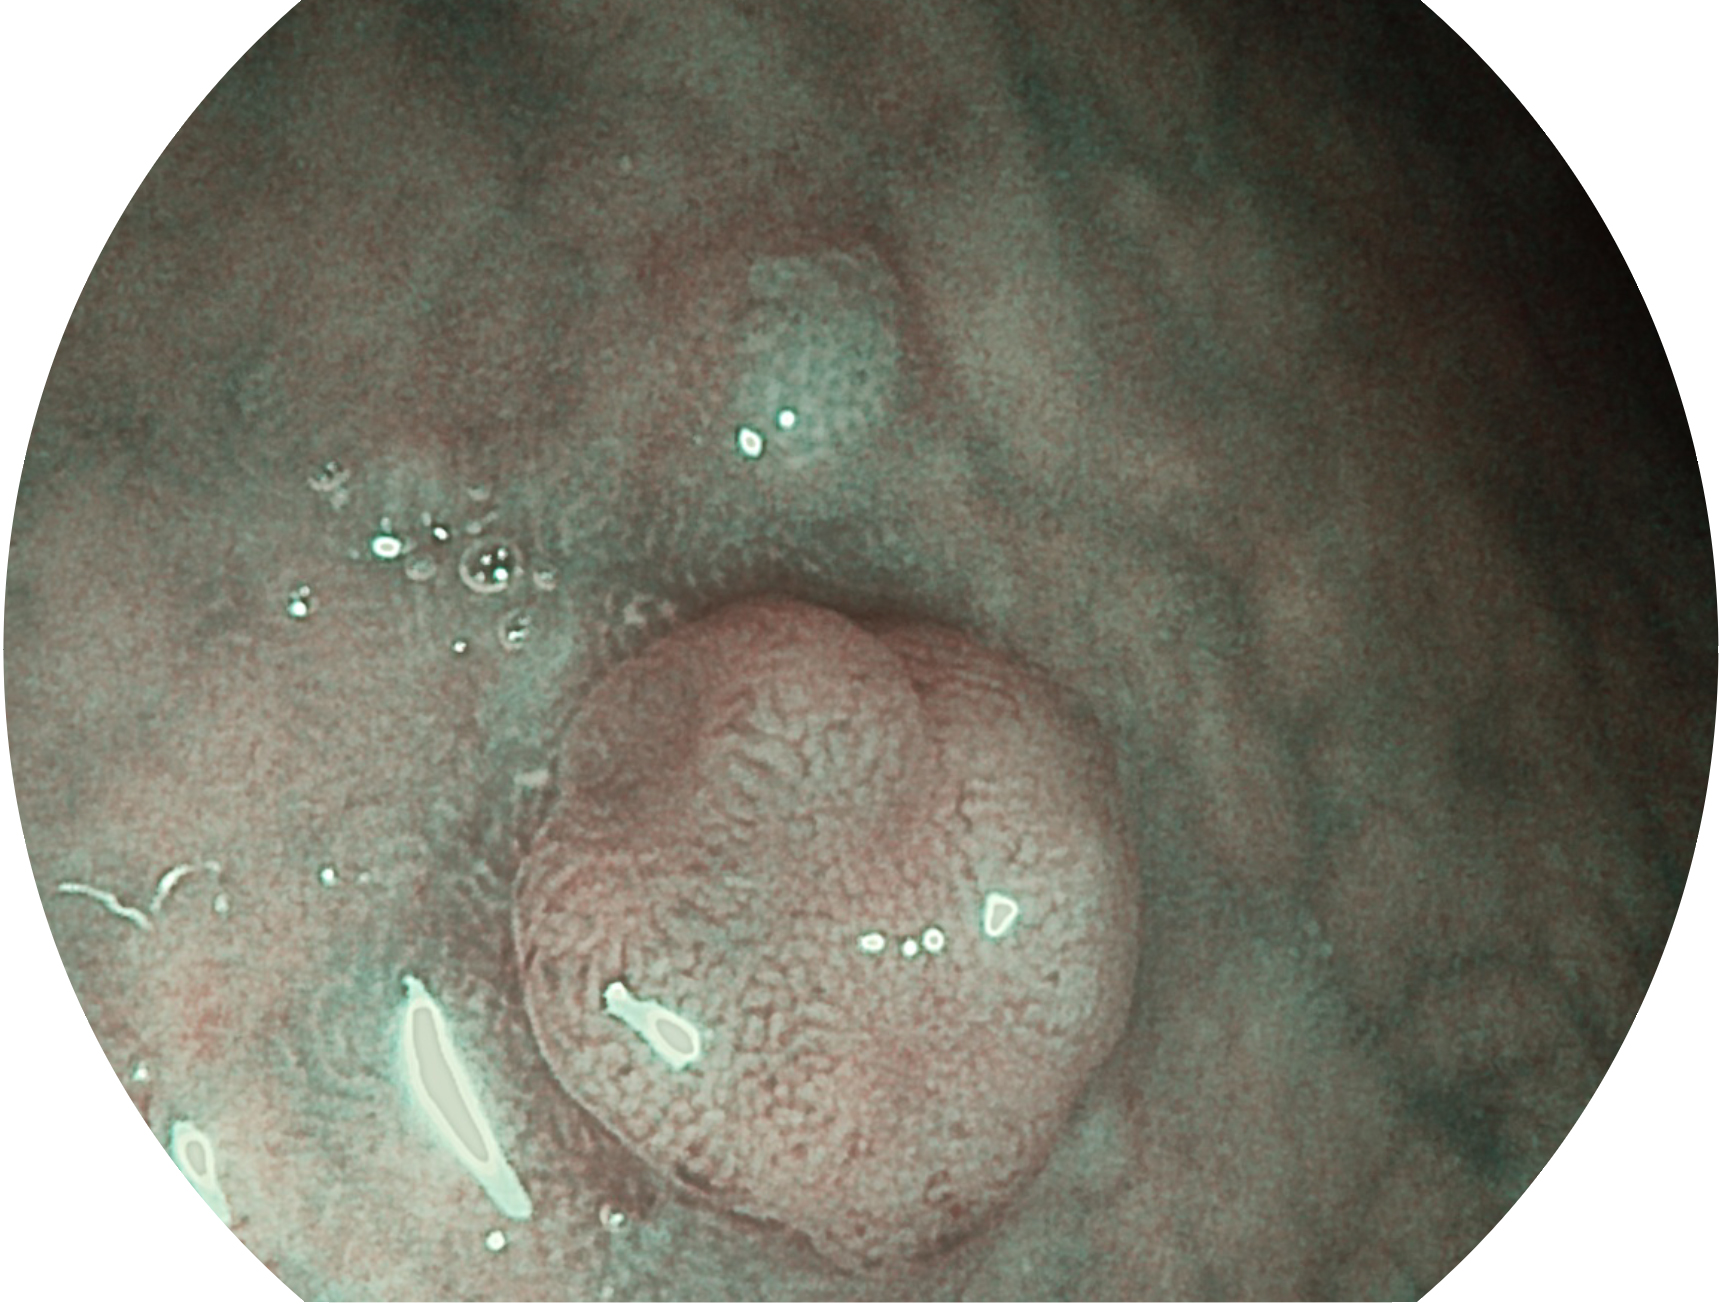

• 白光图像 VIST图像